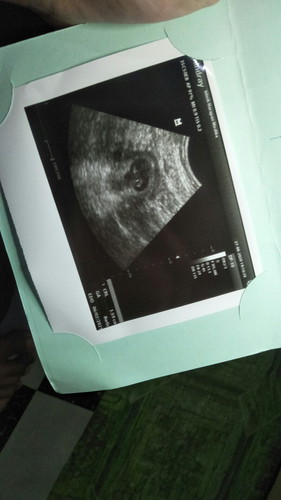

8 minggu tp belom terdengar detak jantungnya, apa yg salah ya

aku baru usg tadi sama juga 8 minggu, alhamdulilah udh kedengeran. coba pas udh 10 minggu cek lagi bund

pas saya blm.. tp usg lg 12week uda kdengeran